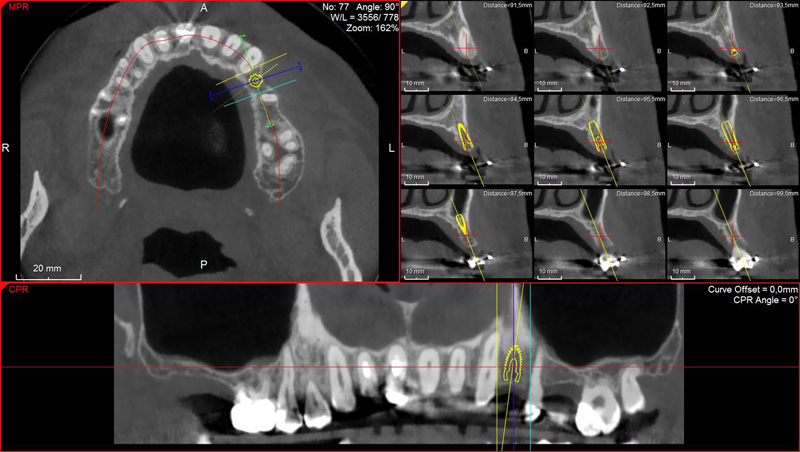

Pro následné plánování využíváme počítačové programy NewTom Implant Planning a coDiagnostiX, které slouží na plánování vhodných pozic pro zavedení implantátů, operačních šablon, kostních bloků, pozdějších protetických náhrad, ...

Lékař si vytvoří všechny typy zobrazení potřebných pro naplánování – tedy 2D snímky (panoramatický), příčné řezy i 3D model.

Vidí zde i důležité anatomické útvary – čelistní dutinu, průběh nervu atd. Po proměření množství kosti – šířky i výšky vybere z databáze vhodný typ implantátu a umístí ho do požadované lokality.

Ihned vidí jeho pozici ve všech 3 rovinách a na všech snímcích i 3D modelu. Může upravovat podle potřeby jeho pozici, sklon atd.

Tento program umožňuje tříprostorovou počítačovou simulaci při plánování pozic implantátů. Součástí programu je i databáze, ve které mohou být uloženy všechny typy implantátů od všech výrobců, včetně jejich délek, průměrů i tvarů.

Vidí zde i důležité anatomické útvary – čelistní dutinu, průběh nervu atd. Po proměření množství kosti – šířky i výšky vybere z databáze vhodný typ implantátu a umístí ho do požadované lokality. Ihned vidí jeho pozici ve všech 3 rovinách a na

všech snímcích i 3D modelu. Může upravovat podle potřeby jeho pozici, sklon atd.

Všechny vybrané a správně umístěné simulované implantáty se ukládají do „počítačové karty“ pacienta s jejich pozicí, délkou, průměrem, typem i sklonem. V programu také lékař navrhuje chirurgické šablony pro řízenou nebo navigovanou implantaci.